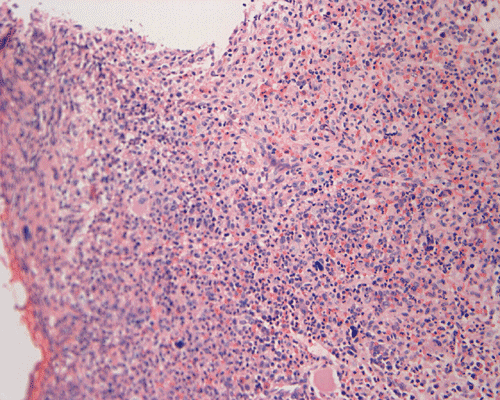

Clinical information: The patient was a 73 year-old man with an itchy skin rash, hepatosplenomegaly, and gastrointestinal bleeding. On admission, his complete blood count (CBC) showed an elevated white count (21,000/cm3) with 25% monocytes and 16% eosinophils, hemoglobin of 9.8 g/dL and 8,000 platelets/cm3. His 24-hour urine histamine was >200 mg/mL (ref 5.6-13.5 mg/mL). A bone marrow biopsy was performed and the representative photomicrographs are illustrated below:

| DIAGNOSIS: Aggressive systemic mastocytosis (WHO classification). |

The patient in the presented case was diagnosed with aggressive systemic mastocytosis, with documented bone marrow, liver and spleen involvement, and succumbed to his disease about two months after the presented biopsy.

Since increased mast cells can be seen in a variety of benign and reactive conditions in the bone marrow. The key morphological features indicating non-reactive, clonal proliferation of mast cells are the abnormal aggregation of mast cells in bone marrow or extracutaneous sites and/or the recognition of atypical mast cells. Mast cell disease should be considered in the differential of cases characterized by extensive myelofibrosis and may be found in a perivascular or trabecular arrangement. As the histological findings can be subtle, knowledge of appropriate clinical information and a high index of suspicion is necessary to identify mastocytosis.

Normal mast cells have a round or oval, centrally located nucleus with uniform distribution of dark purple granules in the cytoplasm. Mast cells are well demonstrated by toludine blue and Giemsa stains, and also by immunohistochemistry for CD 117 or tryptase. Napthol ASD chloracetate esterase also highlight mast cells specifically. Mast cells are also positive for CD45, CD33, and CD68 but these markers are less specific than tryptase. Bone marrow aspirations stained with Giemsa are most useful for recognizing atypia in mast cells. It should, however, note that Giemsa stain may be false negative in formalin fided tissue. Hallmarks of atypia in mast cells include spindling of mast cells, hypogranulation, uneven granule distribution, and nuclear lobulation. Recognition of the so-called mast cell granuloma, in which mast cell aggregrates are associated with lymphocytes and eosinophils can be helpful.

In the bone marrow, three morphologic patterns of mast cell accumulation have been recognized. Type I shows focal clusters of mast cells with preservation of bone marrow fat and other hematopoetic elements. The burden of mast cells is more in Type II and usually shows patchy clusters of mast cell replacing bone marrow in a hypercellular marrow background with osteosclerosis and fibrosis. Type III is diffuse replacement of the marrow space with mast cells, often with circulating mast cells in peripheral blood. It is also important to note that mast cells are easily over looked on routine H and E stain or are mistaken for histiocytes.